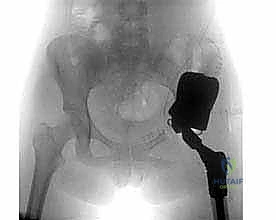

التحدي الأكبر: إعادة بناء الحوض والكتف

لا تقتصر إعادة البناء على الركبة والفخذ. الأورام التي تصيب الحوض أو الكتف تمثل تحدياً جراحياً هائلاً بسبب تعقيد التشريح وقرب الأعضاء الحيوية.

- أورام الحوض: يتم استئصال جزء من عظم الحوض وإعادة بنائه باستخدام غرسات حوضية مخصصة (Pelvic Endoprosthesis)، مما يحافظ على قدرة المريض على المشي ويمنع بتر الطرف السفلي بالكامل (Hindquarter amputation).

- التصوير الشعاعي العادي (X-rays): الخطوة الأولى للكشف عن أي تدمير عظمي أو تكوّن عظمي غير طبيعي.

- التصوير بالرنين المغناطيسي (MRI): الأداة الذهبية لتحديد حجم الورم بدقة، مدى انتشاره في النخاع العظمي، وعلاقته بالأنسجة الرخوة والأوعية الدموية والأعصاب.

- التصوير المقطعي المحوسب (CT Scan): لتقييم القشرة العظمية والبحث عن نقائل في الرئتين.